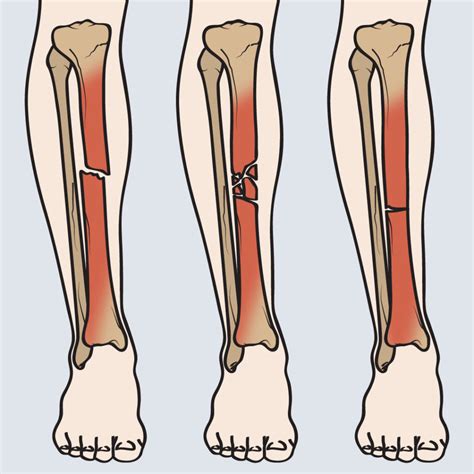

Clinical Differences Between Fracture Types

Not all fractures present with the same intensity. The following table highlights how different levels of injury may manifest:

Type of Fracture Primary Characteristics Weight Bearing

Stress Fracture Dull ache, pain during activity Painful but possible

Simple Fracture Severe pain, swelling, deformity Impossible

Compound Fracture Visible bone, heavy bleeding N/A (Emergency)